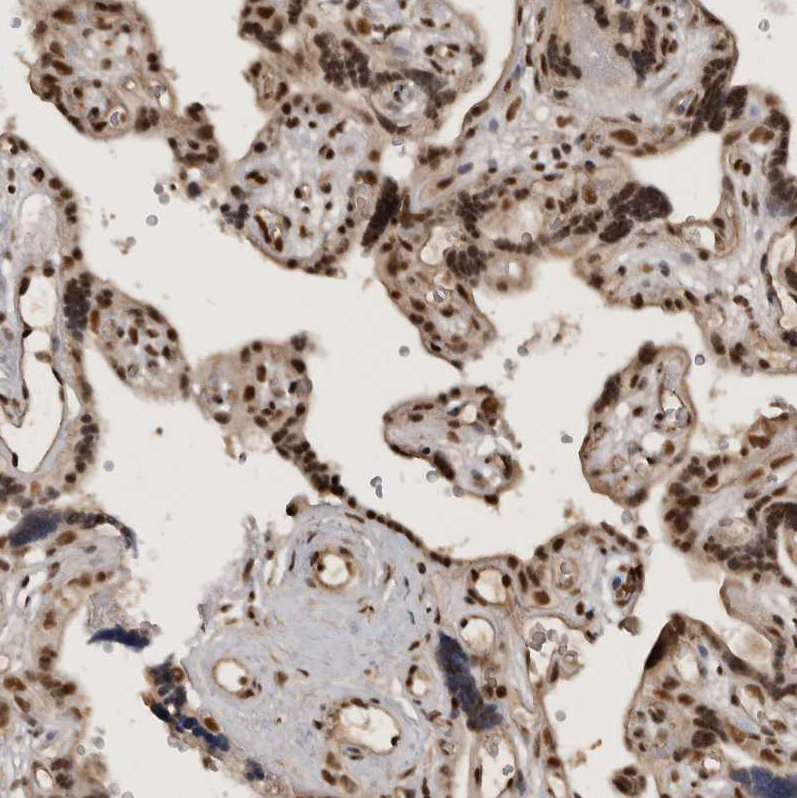

Immunohistochemical staining of human cerebellum, liver, placenta and testis using Anti-CBLL1 antibody HPA021773 (A) shows similar protein distribution across tissues to independent antibody HPA026699 (B).